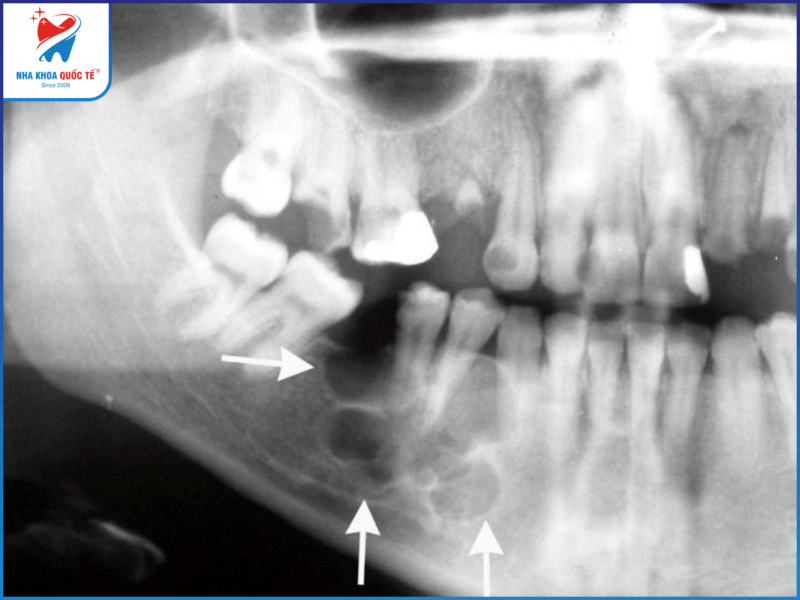

Thông thường u răng là những khối u lành tính, không gây ra triệu chứng và không có những biểu hiện rõ rệt. Hơn một nửa số trường hợp phát hiện ra tình trạng u ở răng khi chụp X quang. Theo nhiều báo cáo khác nhau, tình trạng u ở răng hiếm khi làm gây sưng hàm. Biểu hiện phổ biến nhất của tình trạng u ở răng là sự hiện diện của một chiếc răng vĩnh viễn ngầm hoặc thiếu răng.

U răng thường được phát hiện thông qua chụp X quang

- Chụp X-quang xương hàm

- Chụp CT scan cho u ở răng